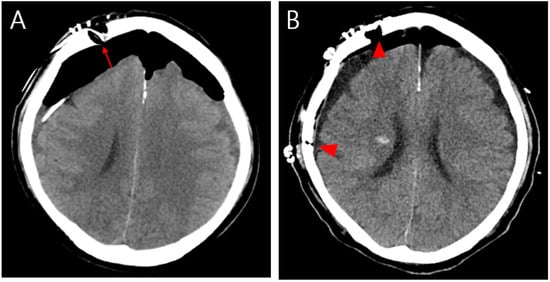

Tension Pneumocephalus Caused by Ethmoidal Roof Fracture: Emergent Surgical Decompression